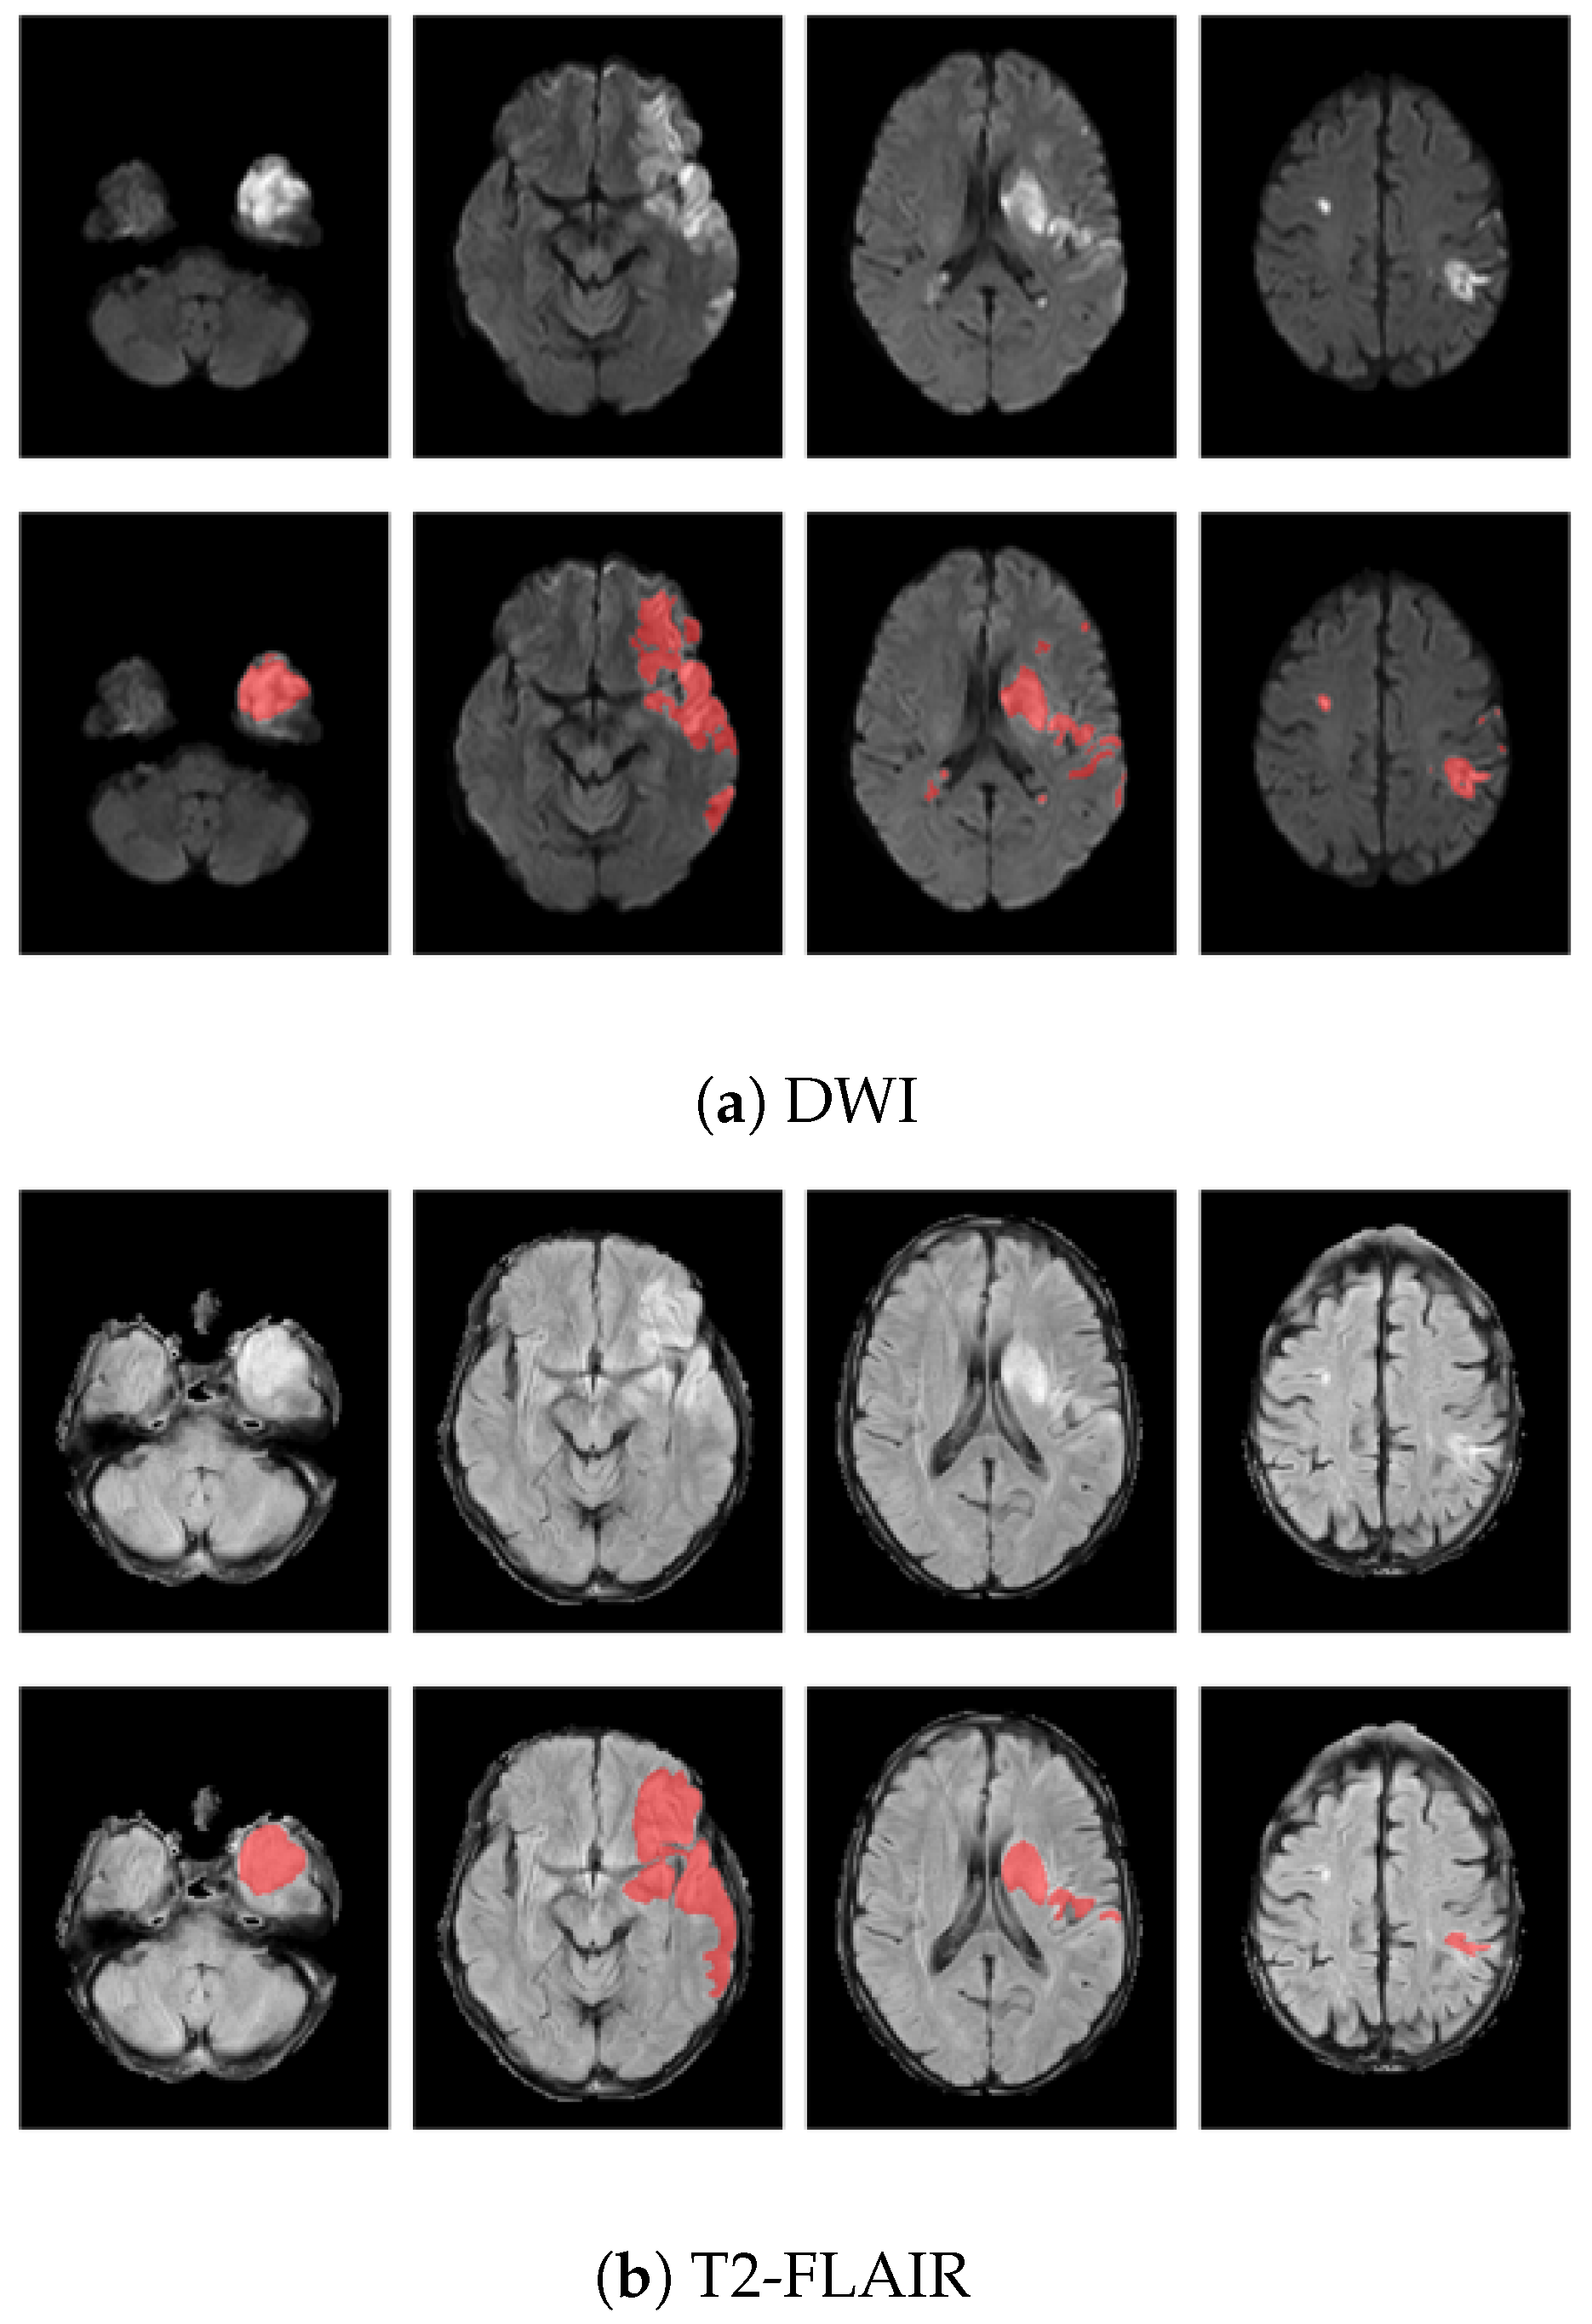

2.2. Image Preprocessing